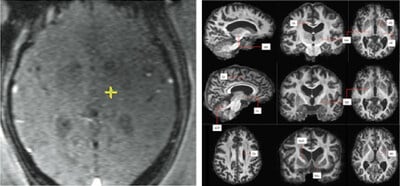

Le Queen Square Imaging Centre a développé une technique d’IRM de pointe appelée FAT1. Cette méthode fusionne différents types de scanners pour obtenir une image très précise du cerveau. Grâce à cette approche, les médecins peuvent cibler exactement la zone responsable du tremblement essentiel.

Traditionnellement, le traitement reposait sur des cartes cérébrales standards. Or, la structure à traiter, appelée Vim, est très difficile à localiser. L’imagerie FAT1 permet une visualisation directe et personnalisée. C’est donc une avancée majeure pour la précision des interventions.